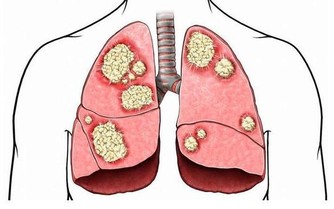

徵兆五:腎臟問題

腎功能不全,會引起腎的病變。腎的病變會讓糖尿病患者腎臟出現一定的不良反應。

徵兆六:腦梗塞腦出血

這是糖尿病並發症中高危一種疾病,如果發現治療不及時,病人會出現暈迷,休克,隨便會出現生命危險。